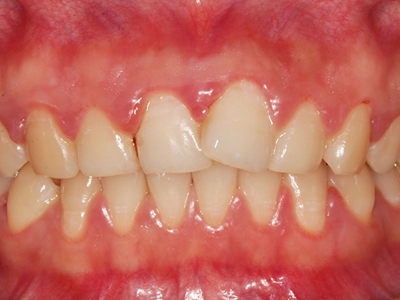

牙龈炎是发生于牙龈组织的炎症,患者可出现牙龈出血伴肿胀、发红、正常形态改变和偶尔不适等症状。本病主要由口腔卫生状况差导致,包括口腔不洁、牙菌斑等,诊断依据临床检查,治疗包括专业牙齿清洁和加强家庭口腔卫生。

牙龈炎可先引起牙齿与牙龈之间的沟(龈沟)加深,然后牙龈充血,炎症围绕一个或多个牙齿,伴牙龈乳头肿胀和易出血。一般无痛,可自行消退,也可维持轻度炎症数年。

牙龈炎常见的病因是口腔卫生差,不良的口腔卫生使牙菌斑沉积于牙齿与牙龈之间,造成龈沟加深,另外牙结石、不良修复体等也可造成牙龈炎的发生。